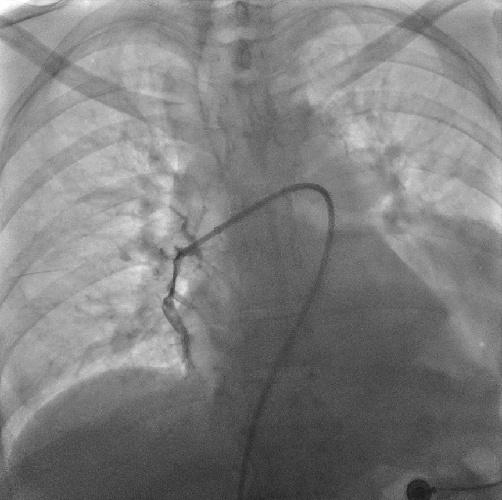

术中造影可见右肺动脉干充盈缺损,

轮廓僵硬,管腔狭窄

导管头顶入血栓中